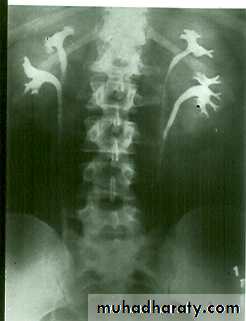

Fusion of lower pole of both kidneys by bridge of renal tissue (isthmus) crossing in front of aorta, spine and IVC.

IVU shows :

The kidneys at low position .

Close to the spine with long axis parallel to the spine .

Mal–rotation manifested by medially directed calyces.

The renal pelvis and ureters are anterior and lateral in position .

Fusion of upper poles is rare.

HORSE –SHOE KIDNEY

HORSE SHOE KIDNEY